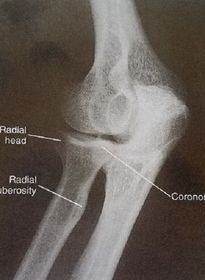

| Lateral Elbow | The elbow is elevated above the level of the shoulder radial head anterior to coronoid - should be superimposed capitulum too proximal to trochlea radial tuberosity seen - hand is pronated |

| Lateral Elbow | Elbow is depressed below the level of the shoulder radial head superimposed by coronoid capitulum too distal to medial trochlea |

| Lateral Elbow | the distal wrist is elevated hand is pronated because you can see the radial tuberosity - should not see that |

| Lateral Elbow Evaluation Criteria | ANATOMY: distal humerus, proximal forearm, entire elbow joint CRITERIA: humeral epicondyles are superimposed radial tuberosity is invisible (if visible the hand is pronated) half of the radial head superimposed by coronoid process Elbow is flexed 90 degrees to see/not see fad pads 3 concentric arcs visible POSITIONING: CR perpendicular @ lateral epicondyle |